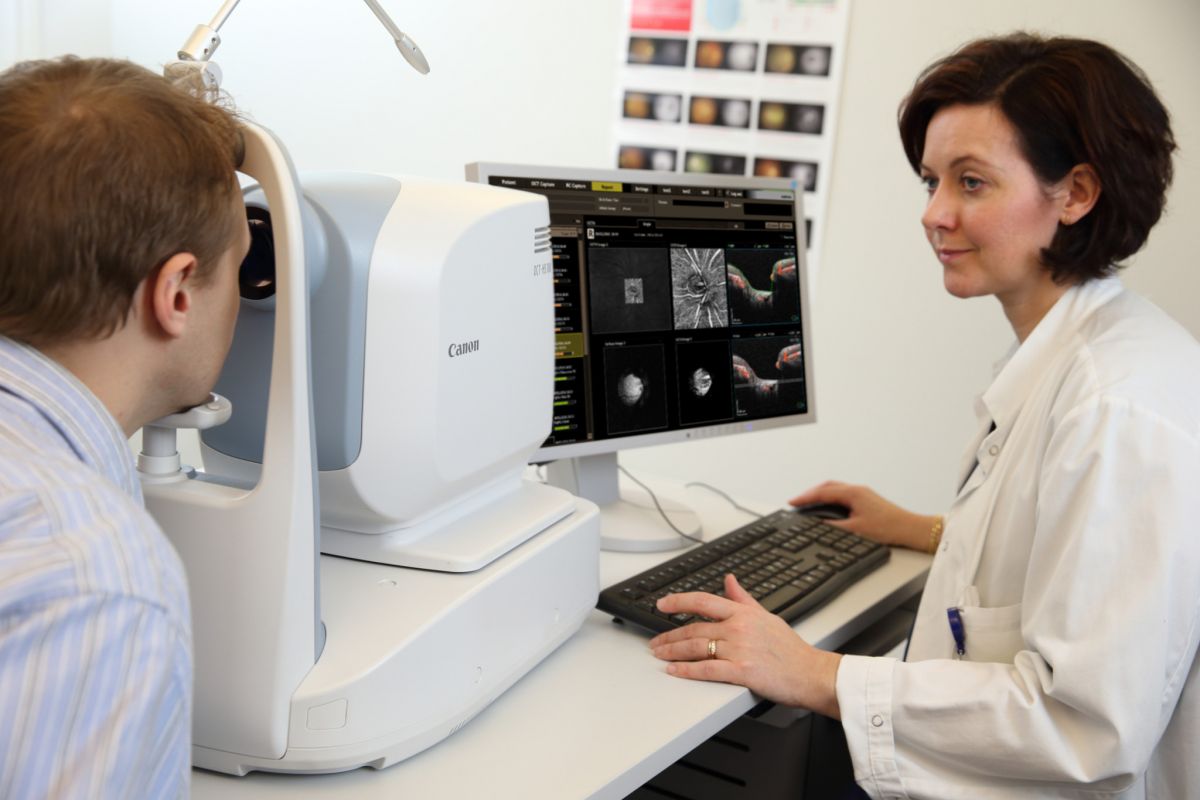

Диагностика зрения: Когерентная томография сетчатки

Раздел: Фотоальбом решений